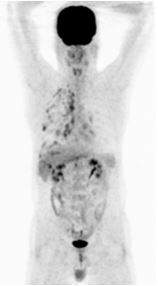

Hình ảnh PET/CT sau 3 đợt điều trị duy trì với Pemetrexed: các khối di căn và hạch không phát triển, max SUV có xu hướng giảm.

Hình ảnh PET/CT sau 3 đợt điều trị duy trì với Pemetrexed: các khối di căn và hạch không phát triển, max SUV có xu hướng giảm.Hình ảnh PET/CT sau 8 đợt hóa chất: nhiều nốt mờ dải rác phổi phải, màng phổi, max SUV = 4,7. Hạch cạnh khí quản 1,5 cm, max SUV = 6,4